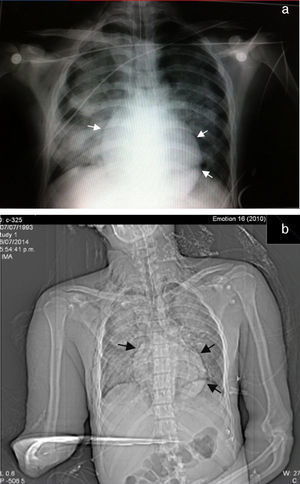

Se decide paso a quirófano por el Servicio de Maxilofacial, 48 h después de su ingreso para reducción abierta con fijación interna de fractura alveololopalatina; durante el postoperatorio inmediato presentó insuficiencia respiratoria, por lo que se realizó intubación orotraqueal para apoyo mecánico ventilatorio y se envió a unidad de cuidados intensivos; se realizó nueva tele de tórax en la que observamos la presencia de múltiples infiltrados bilaterales con relación a contusión pulmonar e imagen sugerente de neumopericardio (fig. 1).

A las 72 h de su ingreso, presentó enfisema subcutáneo en tórax anterior que se extendió a cuello, por lo que se le realizó Tc simple de tórax y de abdomen, con el hallazgo de neumomediastino, contusiones pulmonares bilaterales y neumoperitoneo (figs. 2 y 3). Continuando con apoyo mecánico ventilatorio. Se descartó lesión esofágica por esofagograma con medio hidrosoluble, al igual que lesión traqueobronquial por broncoscopia flexible; además, no se identificaron datos de irritación peritoneal, por lo que se establece como causa de neumomediastino y neumoperitoneo el efecto Macklin.

En el caso de sospecha de neumomediastino, el estudio de gabinete inicial es la radiografía de tórax frontal y lateral, que incluya la región cervical, y en este estudio se pueden identificar el neumomediastino en más del 90% de los casos9. Los signos radiográficos sugestivos de neumomediastino incluyen un trazo radiolúcido que delinea las estructuras mediastinales (más evidente craneal al corazón en el lado izquierdo), eleva la pleura mediastinal y con frecuencia se extiende al cuello o a la pared torácica. En una proyección lateral, este trazo radiolúcido puede delinear la aorta ascendente, el arco aórtico, las áreas retroesternal, precardiaca, periaórtica y peritraqueal. Otros signos radiográficos incluyen el «signo de diafragma continuo», que es gas mediastinal que delinea la superficie superior del diafragma y separa este del corazón; el «signo V de Naclerio», que presenta gas delineando el margen lateral de la aorta descendente y que se extiende lateralmente entre la pleura parietal y la porción medial del hemidiafragma izquierdo y el «signo del anillo alrededor de la arteria», en el cual el gas rodea la porción mediastinal extrapericárdica de la arteria pulmonar derecha10,13.

Los datos radiográficos indirectos incluyen el enfisema subcutáneo torácico y cervical, neumopericardio, neumorretroperitoneo y neumoperitoneo. Se debe buscar intencionadamente la presencia de neumotórax, que puede estar presente hasta en el 84% de los pacientes. La presencia de neumotórax en pacientes con neumomediastino no necesariamente indica lesión de algún órgano del mediastino; de hecho, es un fuerte indicador negativo de lesión esofágica o asociación con lesión de vía aérea10. En el caso clínico que presentamos, hubo evidencia de neumomediastino asociado a neumotórax, sin lesión esofágica ni de la vía aérea demostrada.

En los casos en que la radiografía de tórax es normal (menos del 10%), el estudio de elección es la Tc, que es considerado el «estándar de oro», aun en pacientes con hallazgos radiográficos sugestivos1,10. El efecto Macklin aparece como una colección lineal de aire contigua a la vaina broncovascular y los hallazgos característicos de enfisema intersticial por efecto Macklin, se presentan como una tríada de: 1) enfisema intersticial, 2) a bronquio, y 3) a vaso sanguíneo pulmonar3,16. La Tc respecto al neumomediastino y al neumoperitoneo tiene una alta sensibilidad (> 95%) y especificidad (> 85%) para descartar lesión mayor de tracto aerodigestivo; sin embargo, siempre se debe descartar la posibilidad de lesión esofágica o traqueal con otros métodos diagnósticos10.